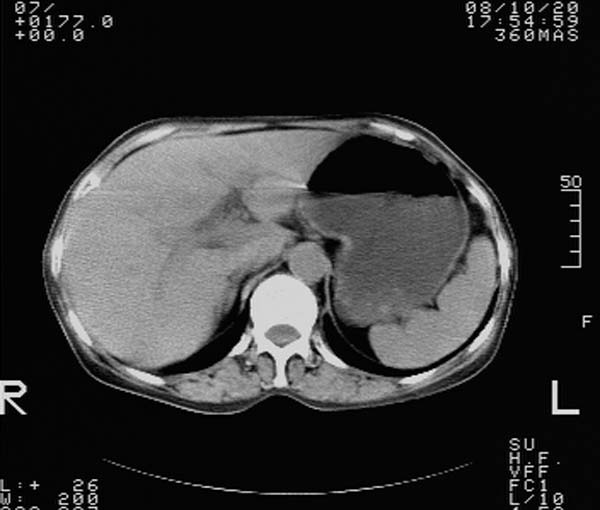

纵隔内及腹膜后广泛淋巴结肿大,脾大,肝内似可见低密度影,结合病史半年前发现颈小结节,逐渐增多增大,现双侧耳后、颌下及颈部表浅淋巴肿大。考虑淋巴瘤。

我们也是首先考虑淋巴瘤。只是外院病检报告是结核。让人迷惑。肝左叶多发低密度占位,没增强不好定论。

纵隔内,双肺门、腋窝及腹膜后多发肿大淋巴结影,肺内小结节影,肝脾体积增大,支持淋巴瘤。肝内多发低密度影,考虑小囊肿。

考虑淋巴瘤肺、肝内转移,脾脏肿大。

纵隔内,双肺门、腹膜后多发肿大淋巴结影及颈部淋巴结肿大,肝脾体积大.结合临床,淋巴瘤可能性大。